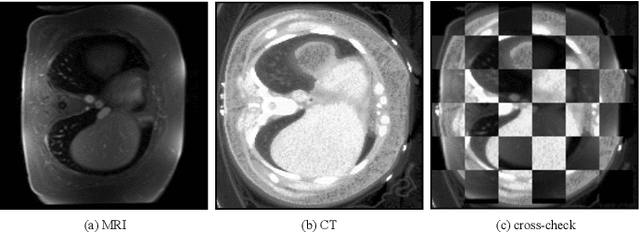

Abstract:Generative models have been widely proposed in image recognition to generate more images where the distribution is similar to that of the real images. It often introduces a discriminator network to discriminate original real data and generated data. However, such discriminator often considers the distribution of the data and did not pay enough attention to the intrinsic gap due to structure. In this paper, we reformulate a new image to image translation problem to reduce structural gap, in addition to the typical intensity distribution gap. We further propose a simple yet important Structure Unbiased Adversarial Model for Medical Image Segmentation (SUAM) with learnable inverse structural deformation for medical image segmentation. It consists of a structure extractor, an attention diffeomorphic registration and a structure \& intensity distribution rendering module. The structure extractor aims to extract the dominant structure of the input image. The attention diffeomorphic registration is proposed to reduce the structure gap with an inverse deformation field to warp the prediction masks back to their original form. The structure rendering module is to render the deformed structure to an image with targeted intensity distribution. We apply the proposed SUAM on both optical coherence tomography (OCT), magnetic resonance imaging (MRI) and computerized tomography (CT) data. Experimental results show that the proposed method has the capability to transfer both intensity and structure distributions.